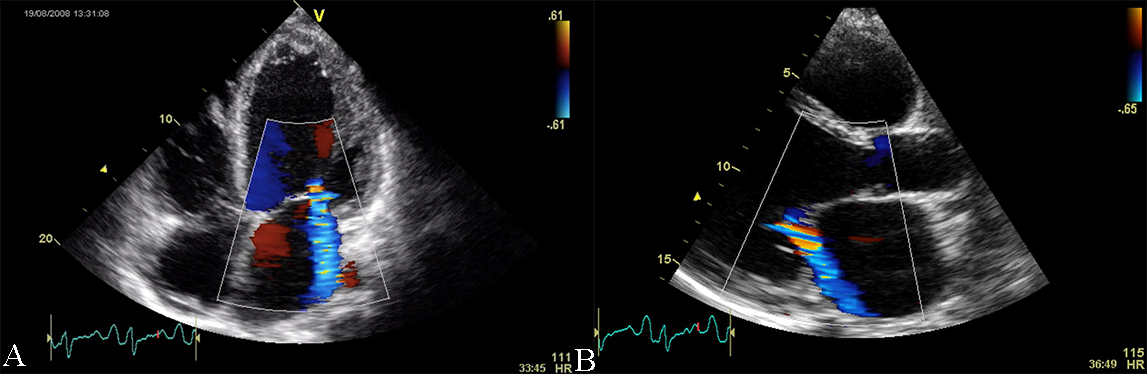

Fig. 4.Echocardiographic aspect of HCM. (A) Apical 4 chamber view systolic frame, showing increased septum thickness. (B) Apical 4 chamber view diastolic frame. (C) Parasternal long-axis view- evidence of systolic anterior motion of the mitral valve. An online video of this patient with HCM is available (Appendix Video 4).